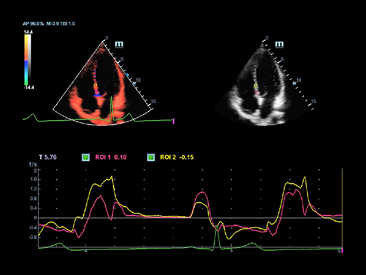

eXceeding Experience

Pengalaman dengan tingkat produktivitas yang tinggi

Pengalaman yang melampaui dalam pemindaian menghasilkan lebih banyak fokus pasien untuk pemeriksaan berkualitas tinggi dalam kejelasan dan kemudahan penggunaan. X-Insight memberikan kemudahan penggunaan yang luar biasa dengan ergonomi yang lebih baik, pemindaian yang lebih mudah, dan manajemen yang fleksibel, bahkan di luar ekspektasi Anda.